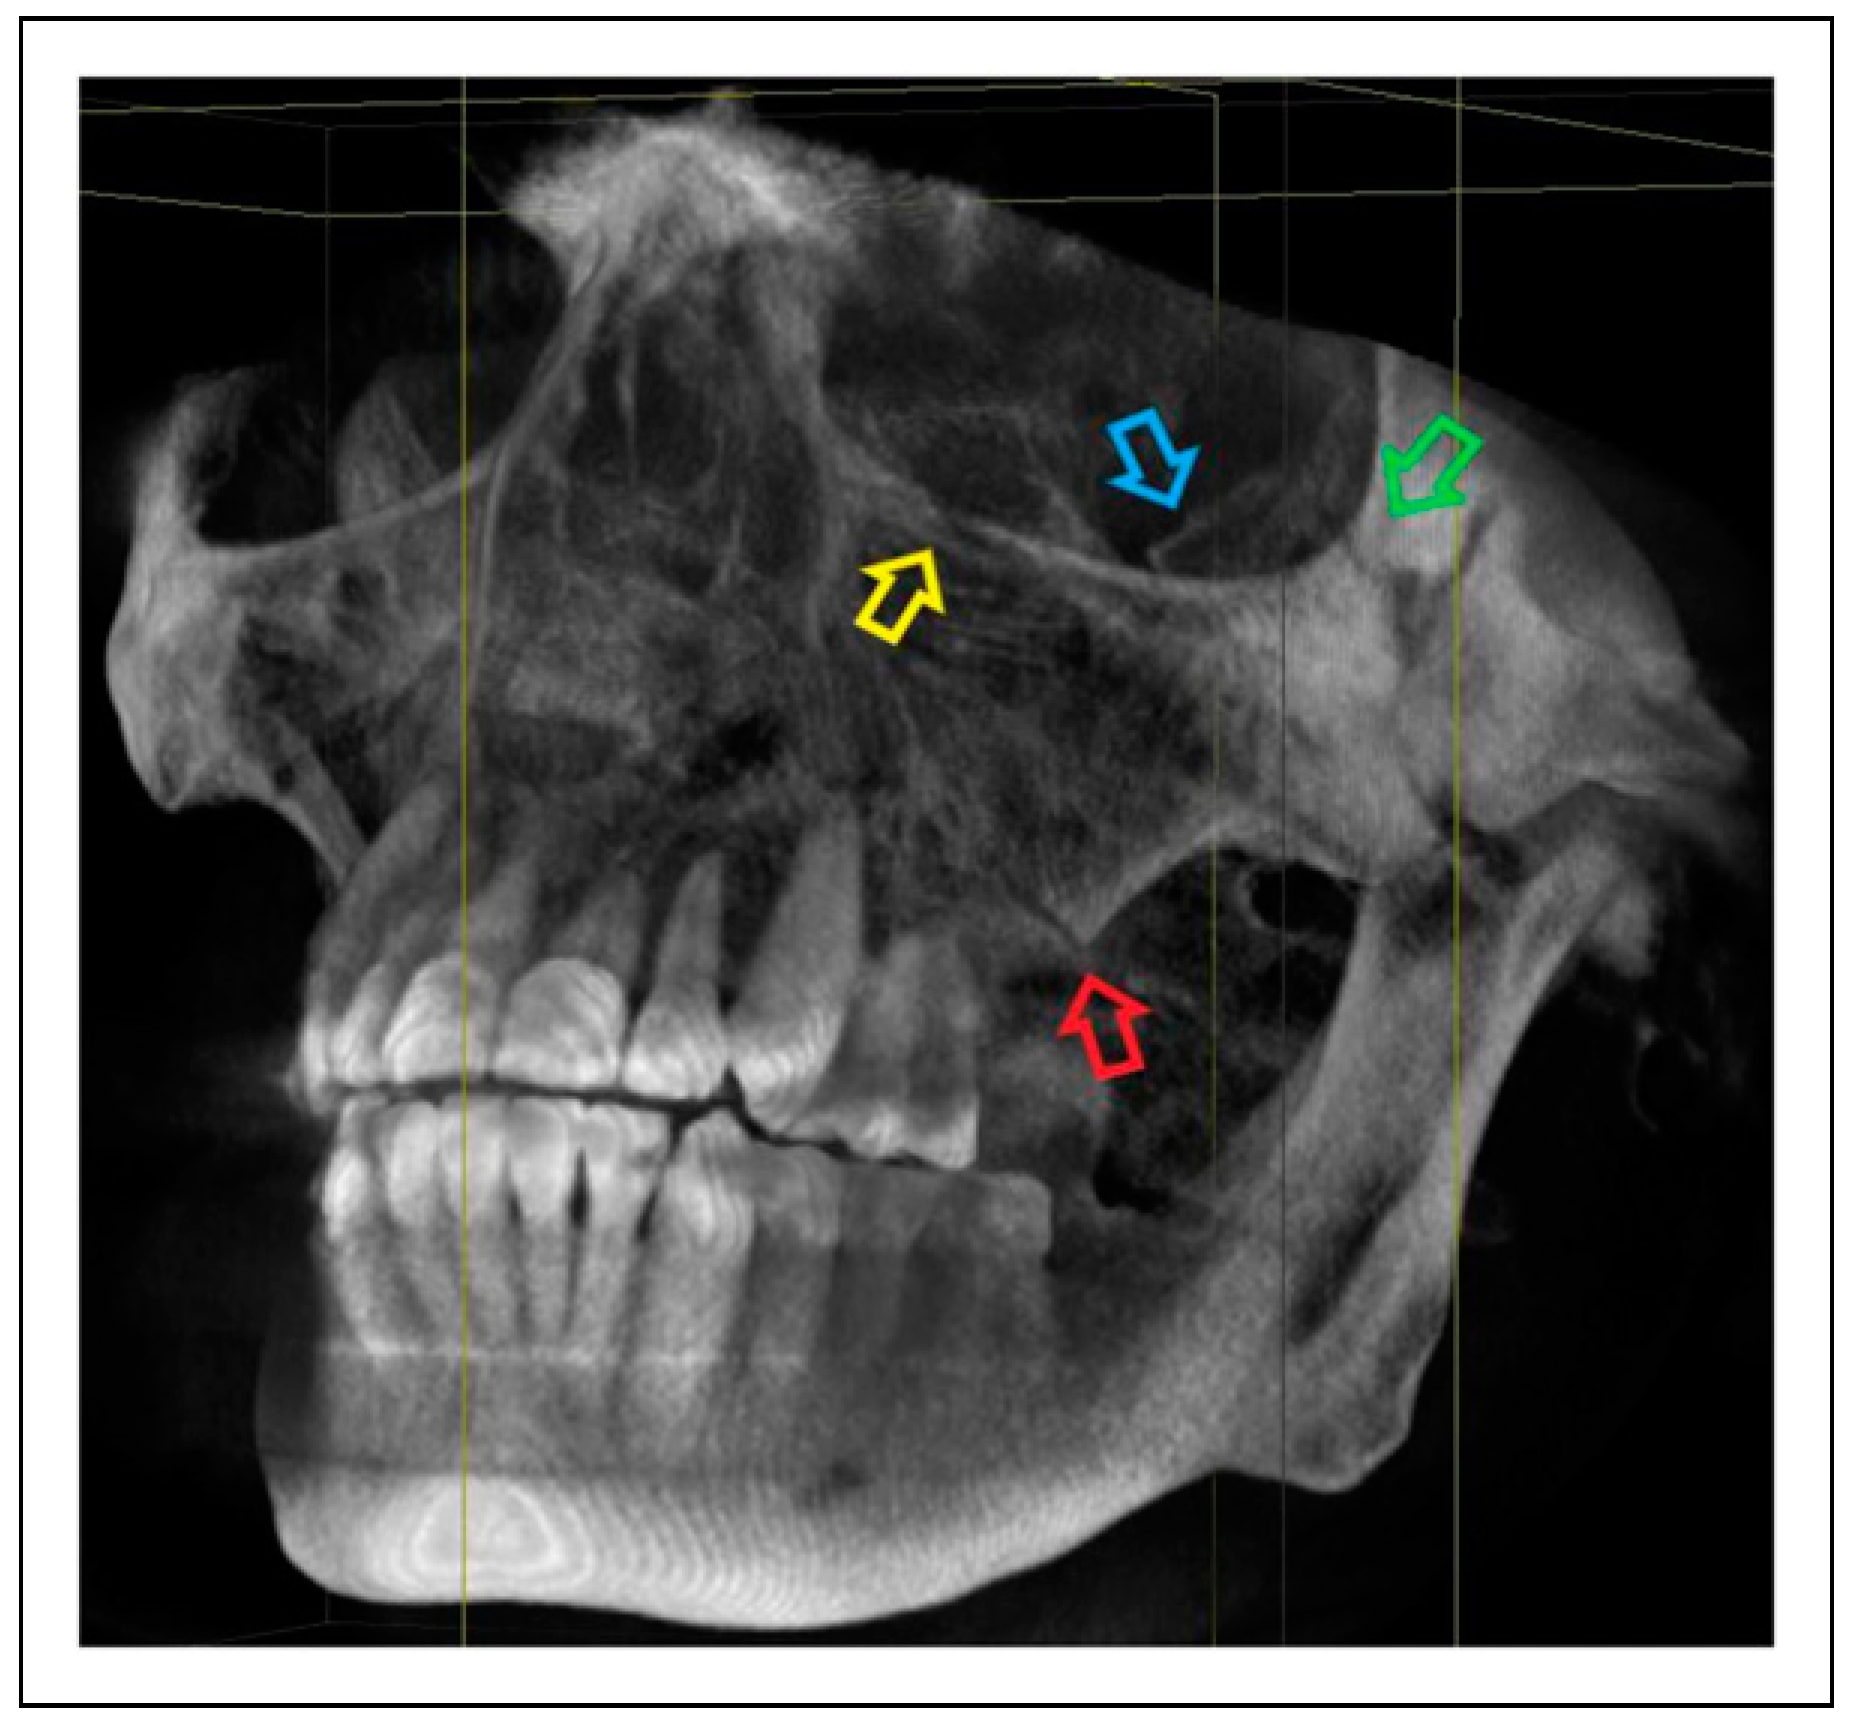

Patterns of ZMO Fractures Regarding the Anatomic Sutures of the Zygoma

- Unisutural fracture (isolated fracture of a single anatomic suture of the zygoma):

- Zygomaticomaxillary suture (ZM)

- Infraorbital rim (IOR)

- Zygomaticofrontal suture (ZF)

- Zygomaticosphenoidal suture (ZS)—the anterolateral orbital floor

- Zygomaticotemporal suture (ZT)

- Bisutural fracture with the following fracture line combinations: